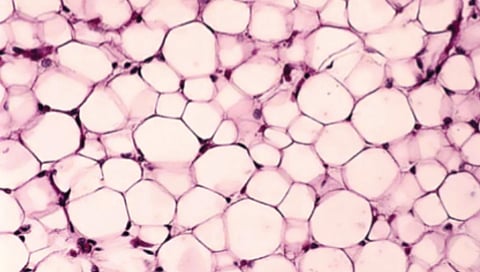

वॉशिंग्टन : माणसाला अद्यापही आपल्याच शरीराची पूर्ण माहिती नाही. त्यामुळेच वेळोवेळी आतापर्यंत अज्ञात असलेल्या काही अवयवांचा शोध लागत असतो. आता शास्त्रज्ञांनी मानवी शरीरात चरबीच्या अनोख्या उपप्रकारांचा शोध घेतला आहे. त्यांच्या कार्यप्रणाली समजून घेतल्यावर असे आढळले की या पेशी लठ्ठपणाशी संबंधित असू शकतात.

‘नेचर जेनेटिक्स’ या वैज्ञानिक जर्नलमध्ये नुकत्याच प्रकाशित झालेल्या या संशोधनामुळे लठ्ठपणाच्या परिणामांवर, जसे की जळजळ, सूज किंवा इन्सुलिन रेझिस्टन्स, नियंत्रण ठेवण्यासाठी नवीन उपचार विकसित करण्याचा मार्ग मोकळा होऊ शकतो, असे शास्त्रज्ञांचे मत आहे. ‘या चरबीच्या उपप्रकारांचा शोध लागणे हे खूपच आश्चर्यकारक आहे,’ असे या संशोधनाच्या सहलेखिका आणि बेन-गुरियन युनिव्हर्सिटी ऑफ नेगेव येथील संगणकीय जीवशास्त्राच्या प्राध्यापिका एस्ती येगर-लोतेम यांनी सांगितले. ‘यामुळे भविष्यात संशोधनाच्या अनेक संधी उपलब्ध होऊ शकतात.‘चरबी पेशी’ या पूर्वीच्या समजुतीपेक्षा जास्त गुंतागुंतीच्या आणि विविध प्रकारच्या असतात, असे कॉर्नेल विद्यापीठाचे पोषण विज्ञानाचे प्राध्यापक डॅनियल बेरी यांनी नमूद केले.

संशोधकांनी असेही लक्षात घेतले आहे की, शरीरातील सर्व प्रकारच्या चरबी समान नसतात. उदाहरणार्थ, पोटाच्या आतील अवयवांजवळ साठणारी व्हिसेरल चरबी ही त्वचेखालील (सबक्युटेनियस) चरबीपेक्षा अधिक धोकादायक असते. व्हिसेरल चरबीमुळे हृदयविकाराचा झटका, स्ट्रोक, मधुमेह, यकृताच्या समस्या आणि इन्सुलिन रेझिस्टन्सचा धोका वाढतो. चरबी पेशींमध्ये नक्की काय घडते हे समजून घेण्यासाठी येगर-लोतेम आणि त्यांच्या सहकार्यांनी ‘सेल अॅटलास’ तयार केला, जो मानवी शरीरातील सर्व पेशींचे नकाशे तयार करण्याच्या जागतिक प्रकल्पाचा एक भाग आहे. संशोधकांनी सिंगल-न्युक्लियस ठछअ सिक्वेन्सिंग तंत्रज्ञानाचा वापर करून चरबी पेशींचे मॅपिंग केले. यामध्ये त्यांनी पेशींच्या ‘आरएनए’चा अभ्यास केला, जो त्या पेशींच्या कार्यक्षमतेबाबत महत्त्वाची माहिती पुरवतो. 15 लोकांच्या पोटातील चरबीच्या पेशींच्या नमुन्यांचे परीक्षण करताना, संशोधकांना आढळले की बहुतांश चरबी पेशी पारंपरिक स्वरूपाच्या होत्या. त्यांचे मुख्य कार्य अतिरिक्त ऊर्जा साठवणे हे होते. मात्र, काही प्रमाणात ‘नॉन-क्लासिकल’ चरबी पेशी आढळल्या, ज्या ऊर्जा साठवण्याव्यतिरिक्त इतर कार्येही करत होत्या. गेल्या काही दशकांत संशोधनाने हे सिद्ध केले आहे की चरबी ऊती फक्त ऊर्जा साठवण्याचे काम करत नाहीत, तर त्या मेंदू, स्नायू आणि यकृताशी संवाद साधत शरीरातील चयापचय, भूक आणि वजन यांचे नियंत्रण करतात. त्यामुळे, चरबी ऊतींमध्ये काही गडबड झाल्यास, त्याचा शरीरातील इतर भागांवरही परिणाम होऊ शकतो, असे येगर-लोतेम यांनी सांगितले.